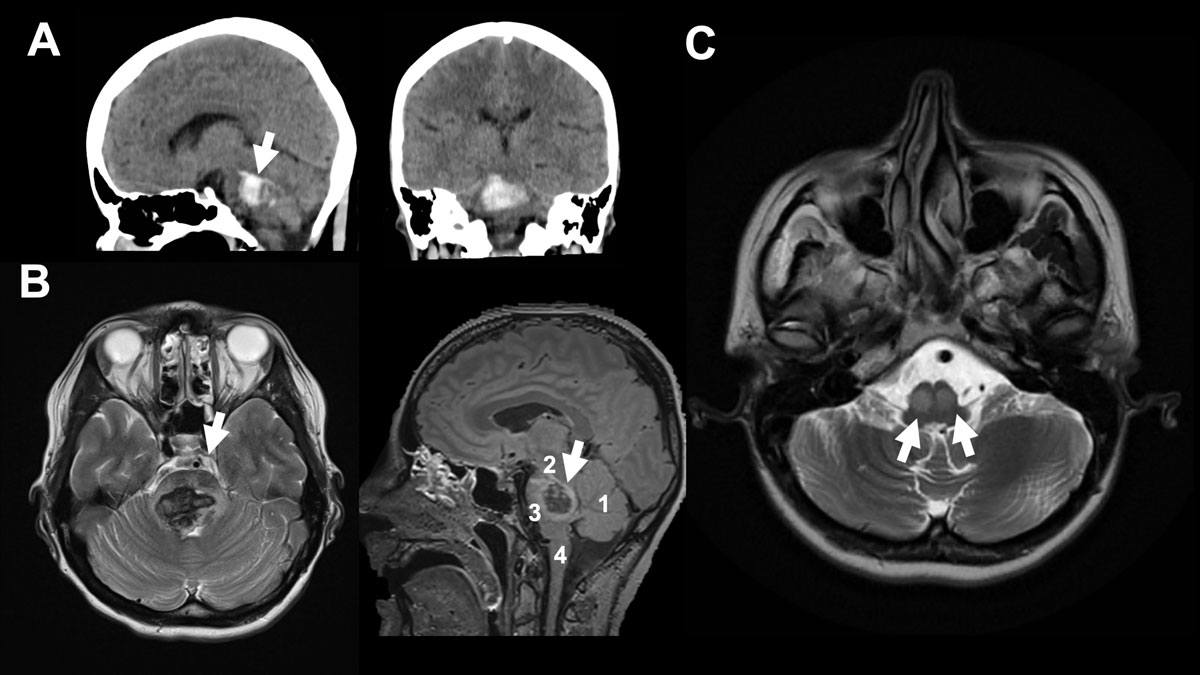

Figure 1 A 37-year-old female patient collapsed after alcohol and drug (cocaine) abuse. The “bilateral tegmental” haematoma was more pronounced on the right, with minimal ventricular extension. The patient’s initial GCS (Glasgow Coma Scale) was 6, with no pupil abnormality, and the patient was intubated in the ED. The patient was a regular cocaine user with a known history of hypertension. On day +4, extubation was unsuccessful due to bulbar palsy. Therefore, tracheotomy was performed on day +6. After decannulation, the patient was discharged to a neurological rehabilitation centre at GCS15 with a horizontal gaze palsy, tetra spasticity, left hypo sensitivity and left facial palsy. A. shows sagittal view and shows axial view of initial CT scan. B. shows initial MRI (axial FLAIR on the left-hand side and sagittal T2 on the right-hand side. Arrow (→) indicates the haemorrhage. 1 indicates cerebellum, 2 mesencephalon, 3 pons and 4 medulla oblongata. C. shows five-month follow-up MRI (axial FLAIR) with hypertrophic olivary degeneration (double arrows →→) caused by the brainstem haemorrhage. The inferior olivaries are part of the dentato-rubro-olivary tract – known as the Triangle of Guillain-Mollaret – connecting the brainstem and the deep cerebellar nuclei. A lesion like hypertrophic olivary degeneration at this triangle may cause modulation problems in spinal cord motor activity and myoclonus.

Brainstem ICH is a medical emergency, and therefore diagnostics must be acquired quickly. MRI has proven to be more accurate than CT imaging at differentiating between haemorrhage ages and therefore at diagnosing older ICHs. For acute ICHs, they offer the same degree of accuracy [13]. Due to its rapid availability, the CT scan remains the imaging modality of choice for evaluating brainstem haemorrhages. In addition, unstable patients in acute distress represent a challenge where MRI is concerned: MRI is risky for them due to its long duration and the restricted access to the patient. Therefore, previous studies have tried to predict outcome depending on radiological CT findings [14–19]. However, MRI can serve as a follow-up diagnostic tool that is not only helpful for prognostication, but also for identifying the precise extension of the lesion, as well as the long-term effects of brainstem bleeding, e.g. olivary degeneration [20] (see also fig. 1).